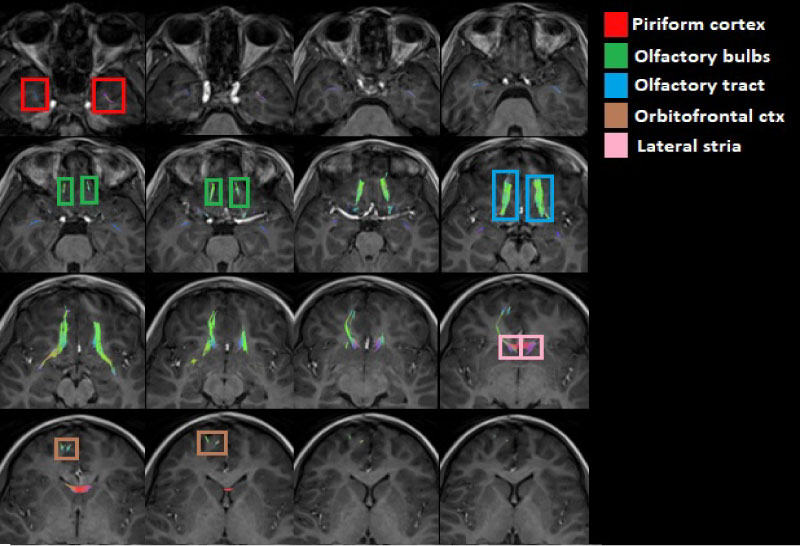

Segmentation of the olfactory pathway

MedINRIA software allows the segmentation of the olfactory tracts by placing ROIs on the tracts of interest with a deterministic tracking algorithm [16], which makes it possible to isolate the tracts of interest from the total tracts in the human brain. In order to segment this functional pathway, ROIs were placed at the level of the base of the frontal lobe, where the olfactory bulbs are located [17] (Figure 1).

Figure 1: ROIs on the olfactory bulbs where information about odours. a) Axial view of the tracts corresponding to the olfactory bulbs, b) Axial view of the ROIs placed on the olfactory bulb, c) Coronal view of the tracts corresponding to the olfactory bulbs and d) Coronal view of the ROIs on the olfactory bulb. View Figure 1

The MedINRIA software followed tracts corresponding to the limbic system, specifically tracts of the circulated gyri, for which it was necessary to delimit the tracts associated with the olfactory path using regions of avoidance (ROA's) placed on the cingulated gyri and the corpus callosum, which, combined with the ROI's, made it possible to delimit the regions associated with the olfactory pathway.

In this way, the olfactory path corresponding to the tracts of the olfactory bulbs, the olfactory cortex and the orbitofrontal cortex of the brain were characterized. The objective of being able to visualize the WM tracts in a 3D image is to be able to visualize the connectivity between the different brain zones corresponding to the olfactory system, in addition to representing an advantage for the doctor and their corresponding clinical interpretation. The measure of the diffusion parameters of the total tracts that the MedInria software provides (FA and ADC) were measured; these tracts can be seen in (Figure 2).